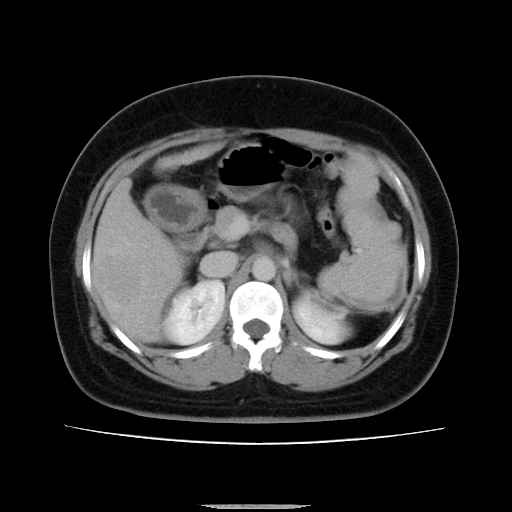

标题: CT14225:女性46岁。当地B超示肝内占位,来我院作CT检查。请 [打印本页]

标题: CT14225:女性46岁。当地B超示肝内占位,来我院作CT检查。请

动脉期病原灶明显强化高于肝密度且中央有无强化区,静脉期强化程度下降明显,延迟低于肝密度,考虑肝腺瘤可能性大,

此患者虽然符合快进的特点,却不符合快出的特点,因为门脉期几乎是等密度,不符合肝癌的增强表现,所以我考虑肝局灶性结节增生可能性大